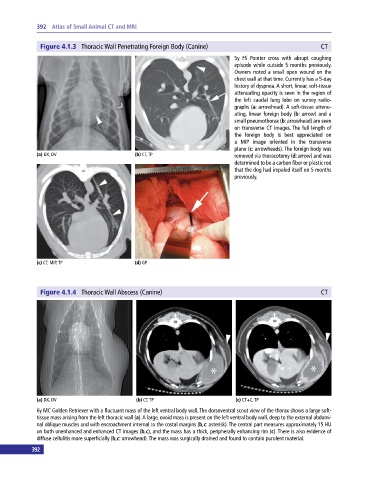

Figure 4.1.3 Thoracic Wall Penetrating Foreign Body (Canine) CT

5y FS Pointer cross with abrupt coughing

episode while outside 5 months previously.

Owners noted a small open wound on the

chest wall at that time. Currently has a 5‐day

history of dyspnea. A short, linear, soft‐tissue

attenuating opacity is seen in the region of

the left caudal lung lobe on survey radio-

graphs (a: arrowhead). A soft‐tissue attenu-

ating, linear foreign body (b: arrow) and a

small pneumothorax (b: arrowhead) are seen

on transverse CT images. The full length of

the foreign body is best appreciated on

a MIP image oriented in the transverse

plane (c: arrowheads). The foreign body was

(a) DX, DV (b) CT, TP removed via thoracotomy (d: arrow) and was

determined to be a carbon fiber or plastic rod

that the dog had impaled itself on 5 months

previously.

Figure 4.1.4 Thoracic Wall Abscess (Canine) CT

6y MC Golden Retriever with a fluctuant mass of the left ventral body wall. The dorsoventral scout view of the thorax shows a large soft‐

tissue mass arising from the left thoracic wall (a). A large, ovoid mass is present on the left ventral body wall, deep to the external abdomi-

nal oblique muscles and with encroachment internal to the costal margins (b,c: asterisk). The central part measures approximately 15 HU

on both unenhanced and enhanced CT images (b,c), and the mass has a thick, peripherally enhancing rim (c). There is also evidence of

diffuse cellulitis more superficially (b,c: arrowhead). The mass was surgically drained and found to contain purulent material.